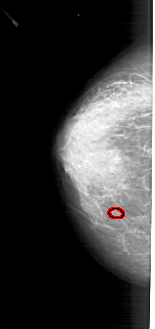

FILE: A_1280_1.LEFT_CC.OVERLAY

TOTAL_ABNORMALITIES 1

ABNORMALITY 1

LESION_TYPE CALCIFICATION TYPE PLEOMORPHIC DISTRIBUTION CLUSTERED

ASSESSMENT 4

SUBTLETY 2

PATHOLOGY BENIGN

TOTAL_OUTLINES 1

BOUNDARY